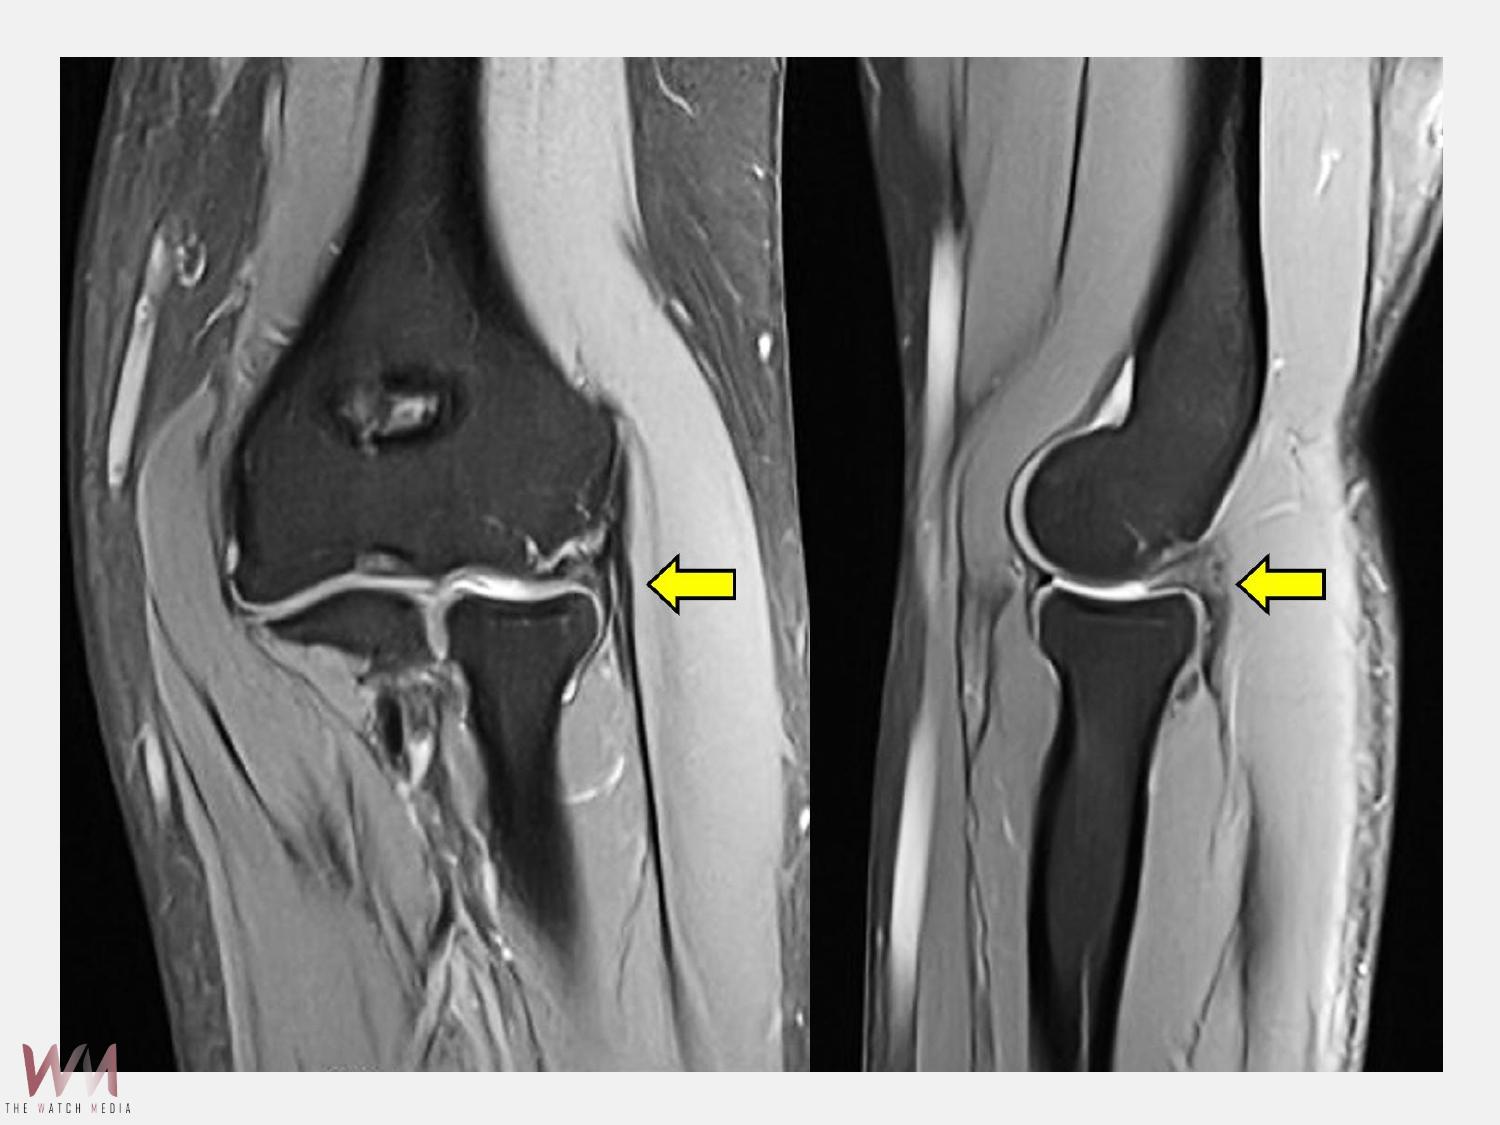

陳重宇醫師說,外側手肘疼痛並非全是「網球肘」,其他常見原因包括:韌帶或關節囊損傷、剝離性軟骨炎、骨刺或退化性關節炎、滑膜皺襞症候群(synovial plica syndrome)和神經壓迫性疼痛。針對手肘的結構性病因,微創關節鏡手術是一個安全且效果良好的選擇。以C小姐為例,手術透過關節鏡直接觀察肘關節內部結構,精準鬆解發炎的肌腱附著點,並清除增生的滑膜皺襞。手術僅需數個約1公分的小切口,創傷小、出血少,術後疼痛明顯減輕,復原速度快。